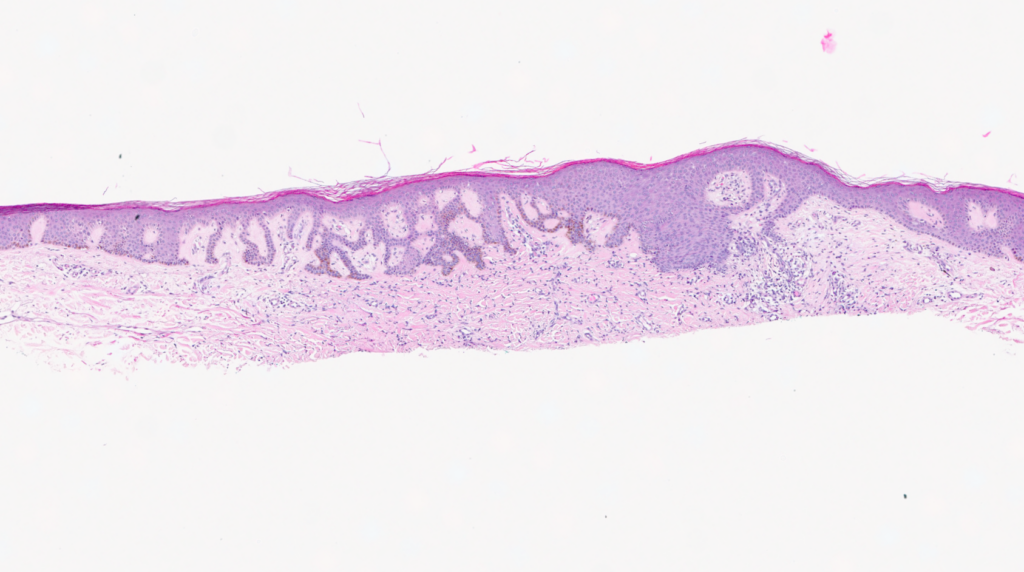

This Week's Slide

🧑⚕️ Patient

- 53-year-old male

📍 Presentation

- Biopsy from the right calf for assessment of an atypical pigmented skin lesion.

💬 What’s the diagnosis?

- Dermatofibroma